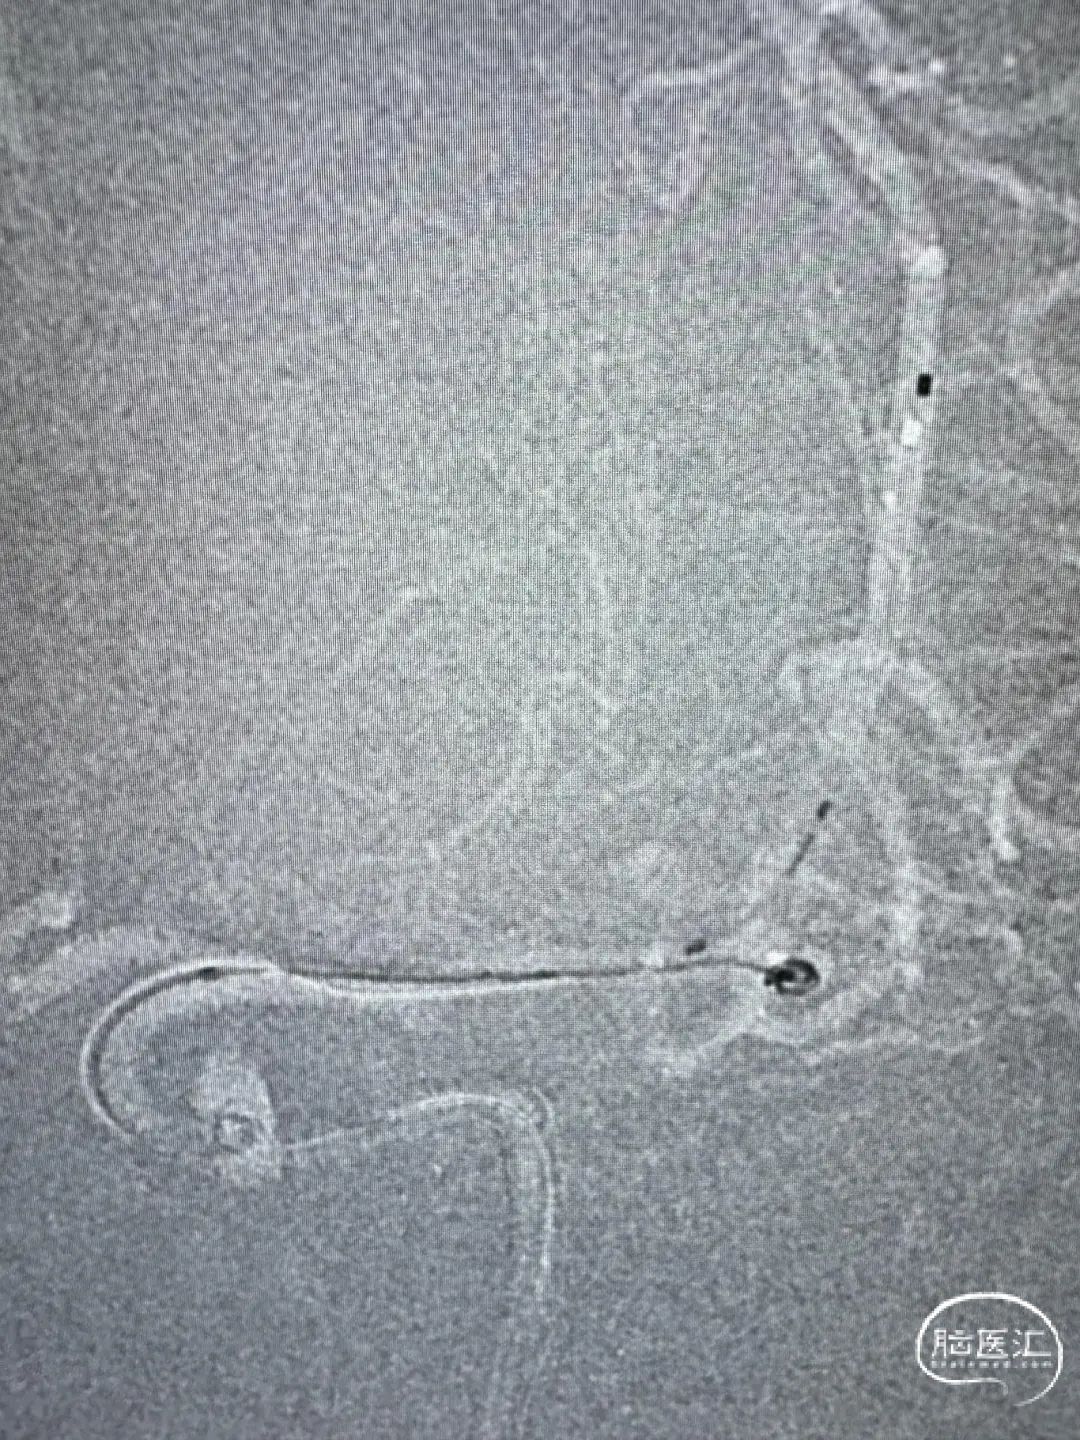

两根Echelon-10分别备用支架及弹簧圈,首圈2.5mm×6cm(ev3)。

Atlas支架3mm×15mm,继续填圈1.5mm×4cm(Galaxy G3 MINI)及1.5mm×4cm(ev3)。

一根Echelon-10备选颞干,另一根Echelon-10送入瘤腔。

首圈1mm×3cm(ev3),最后用1mm×2cm(ev3)收尾。